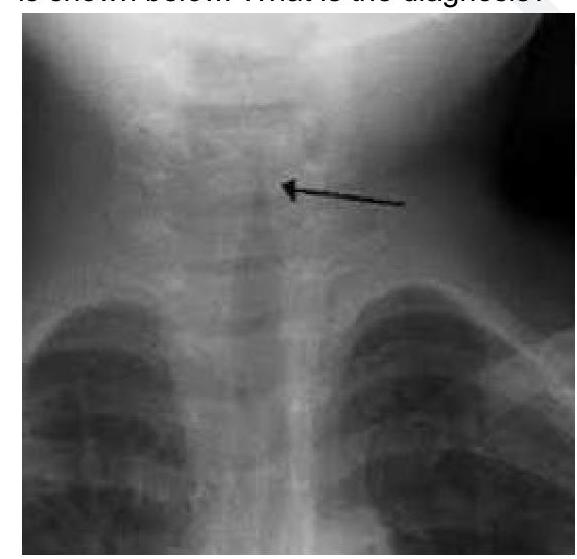

Explanation: ***Acute Laryngotracheobronchitis*** - The combination of **low-grade fever** and **stridor** in a 2-year-old child strongly suggests **croup**, which is medically known as acute laryngotracheobronchitis. - Croup is characterized by **inflammation** of the larynx, trachea, and bronchi, often presenting with a **barking cough** and inspiratory stridor. The X-ray image would show the characteristic **steeple sign**. *Acute Bacterial Tracheitis* - This is a more severe bacterial infection that can present with stridor but typically shows **higher fever**, **toxic appearance**, and rapid clinical deterioration. - Unlike croup, bacterial tracheitis patients appear **more ill** and may have **purulent secretions** requiring more aggressive management. *Acute Epiglottitis* - A serious condition characterized by **rapid onset of high fever**, **dysphagia**, drooling, and a **"tripod" position**, which are not indicated by the given symptoms. - The stridor in epiglottitis is typically quieter and may indicate more severe airway obstruction compared to the characteristic stridor of croup. *Foreign Body aspiration* - While foreign body aspiration can cause stridor, it is typically an **acute event** with a sudden onset of choking, coughing, and respiratory distress. - There is no mention of a choking episode or sudden onset, and a low-grade fever is less typical for an uncomplicated foreign body aspiration.

A 2 year child presented with low grade fever and stridor. What is the likely diagnosis?